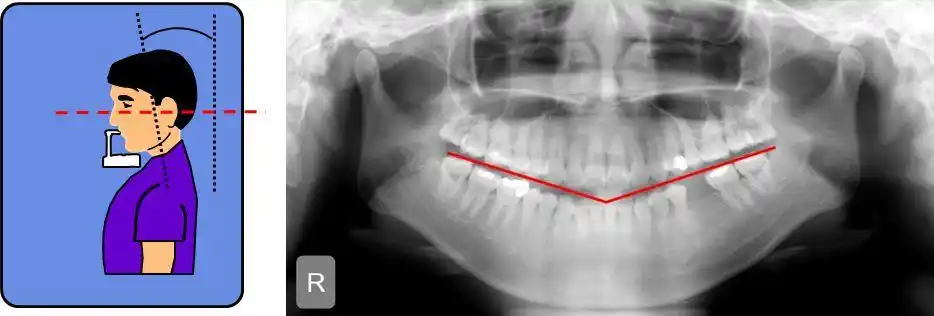

伯爵cbct影像篇③口腔全景片认知